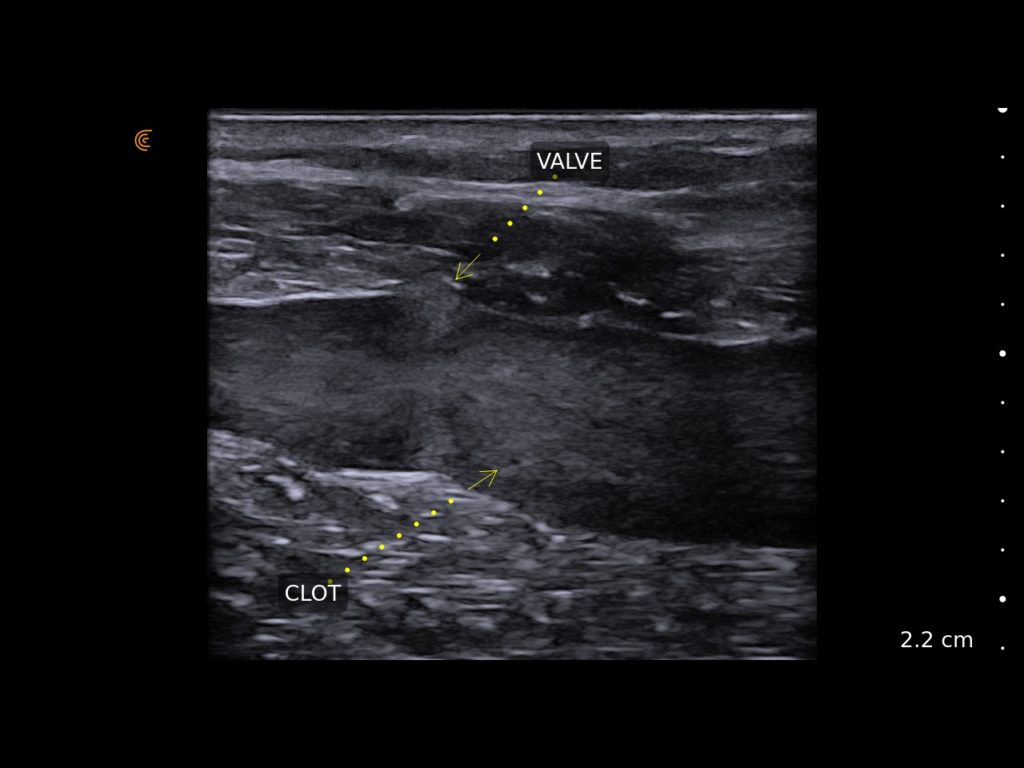

• Rapidly evaluate patients for deep vein thrombosis

DVT